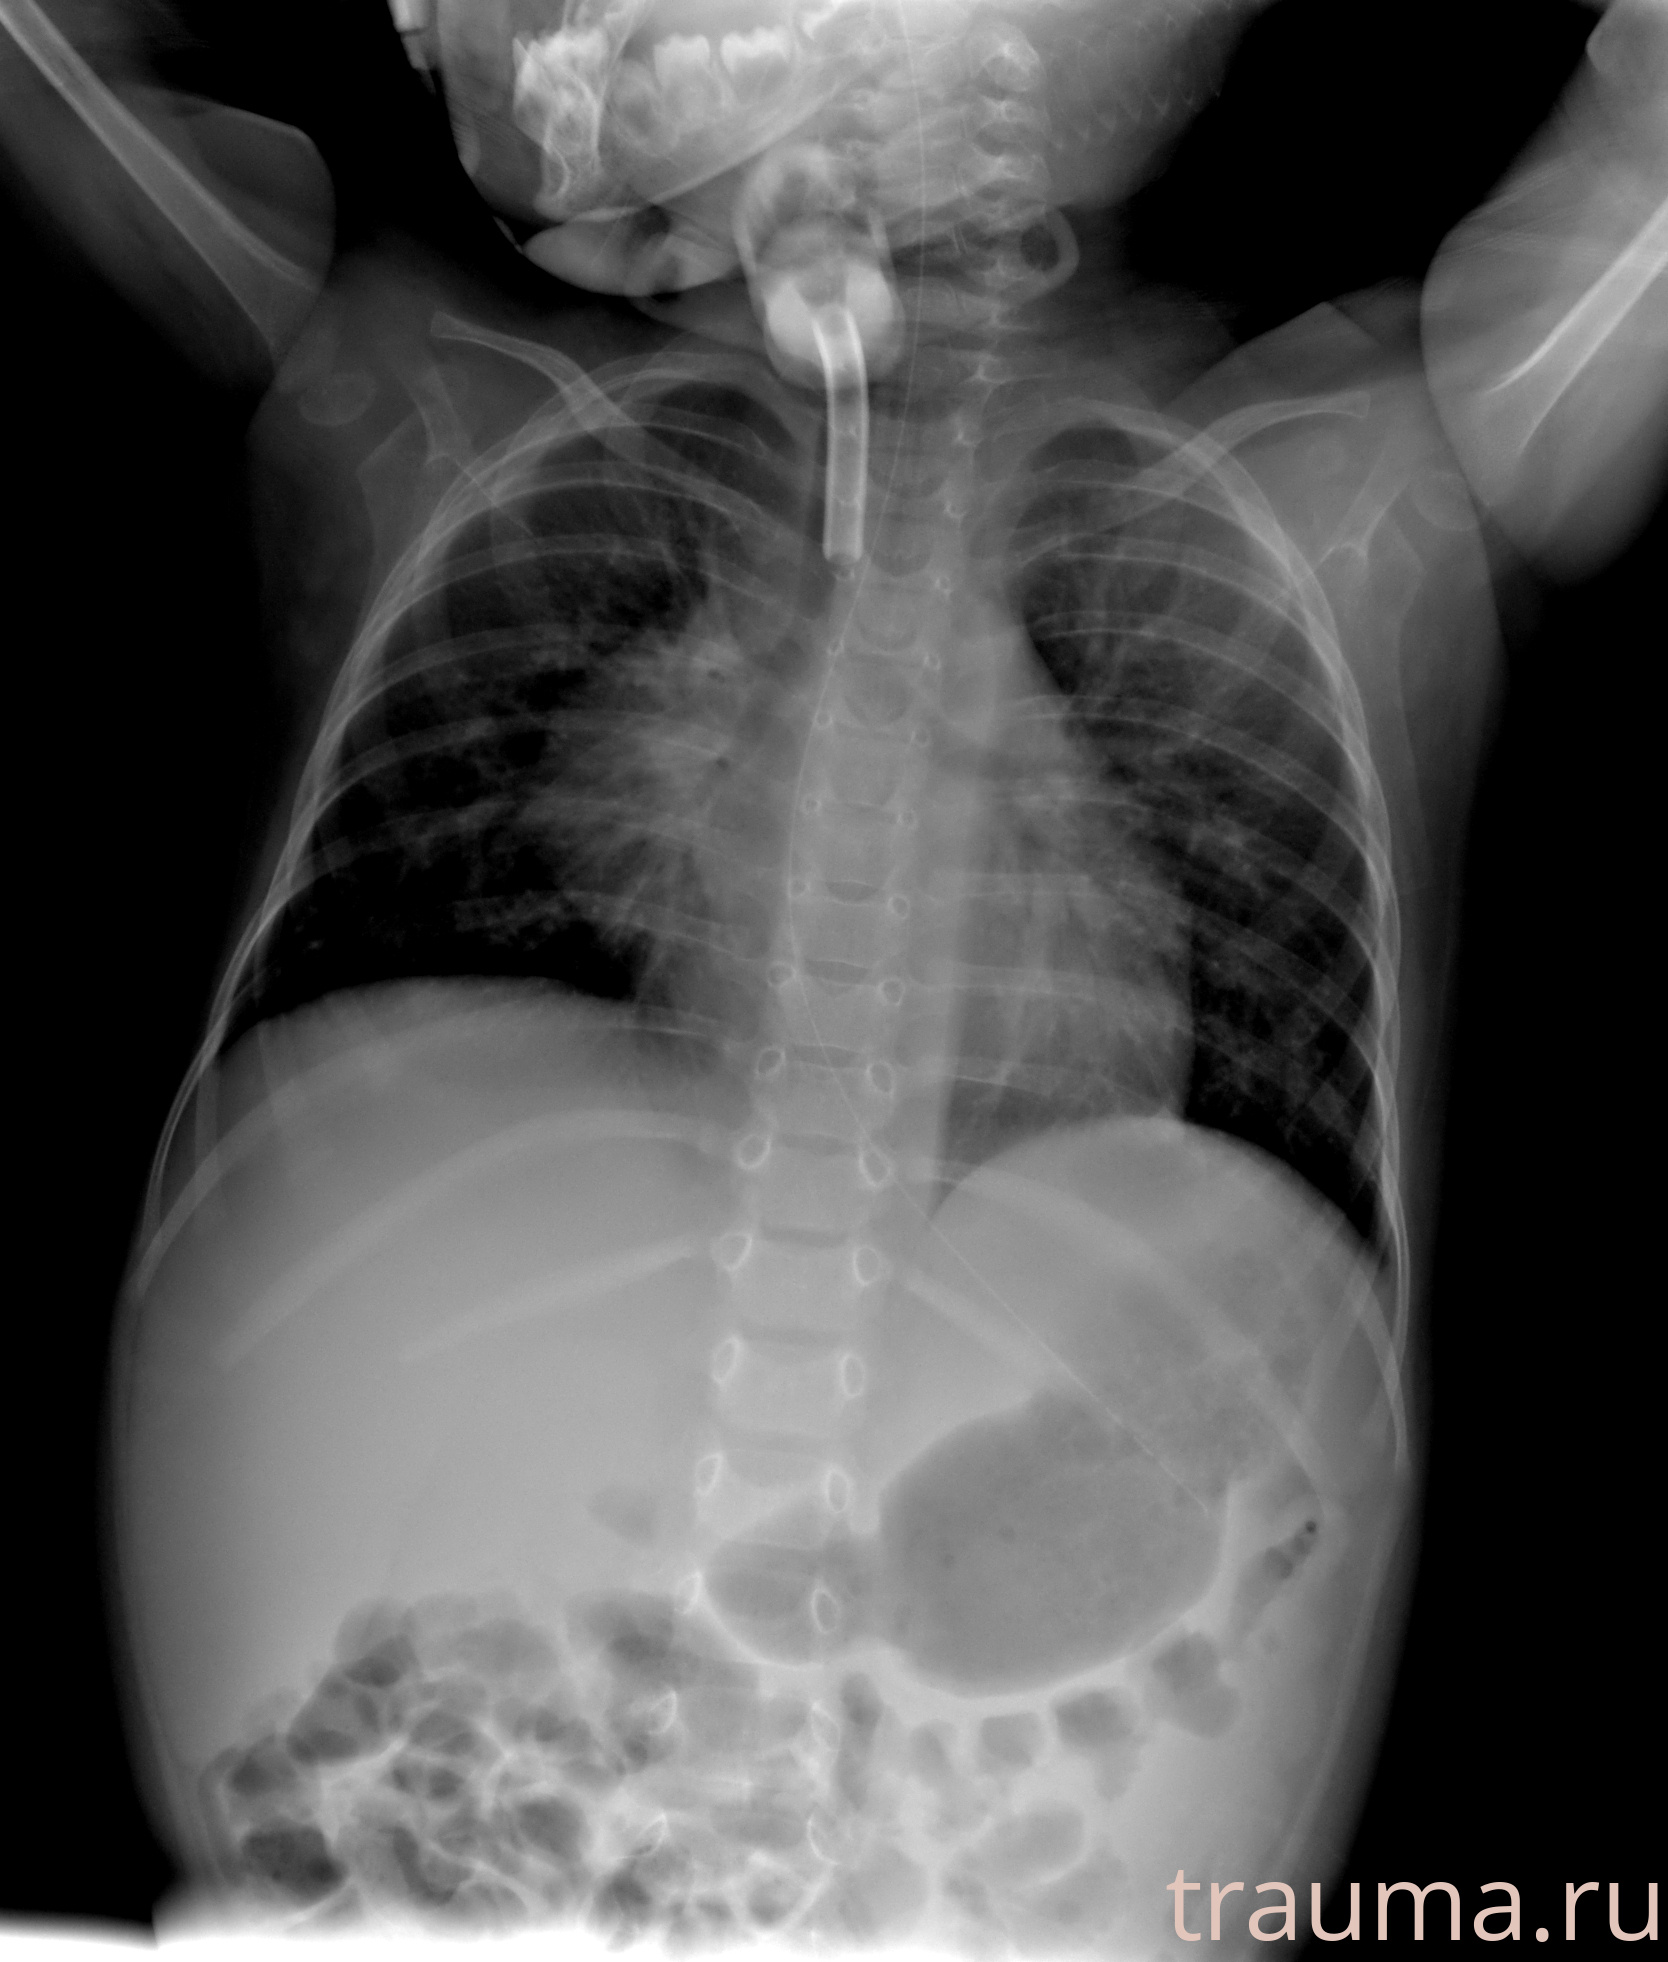

Рентгенограммы

Рентген на дому: по вашему адресу приезжает врач-рентгенолог, травматолог-ортопед с мобильным рентгеновским аппаратом, проводит диагностику травмы или заболевания, делает необходимые рентгенограммы, дает рекомендации по дальнейшему лечению. Получить качественные снимки в домашних условиях возможно благодаря уникальной методике, разработанной МосРентген Центром для института  Склифосовского